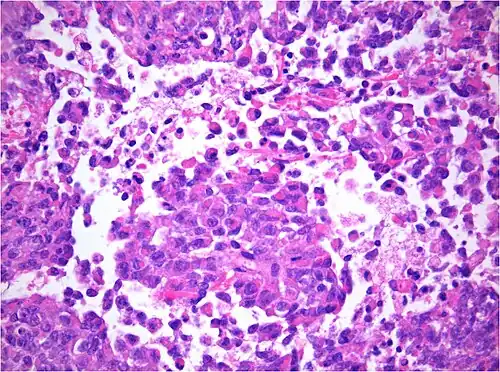

AT/RT and rhabdoid tumor share the term "rhabdoid" because under a microscope, both tumors resemble rhabdomyosarcoma.

AT/RT Histology with numerous rhabdoid tumor cells -

Histology

The tumor histopathology is jumbled small and large cells. The tissue of this tumor contains many different types of cells including the rhabdoid cells, large spindled cells, epithelial and mesenchymal cells, and areas resembling primitive neuroectodermal tumor (PNET). As much as 70% of the tumor may be made up of PNET-like cells. Ultrastructure characteristic whorls of intermediate filaments are seen in the rhabdoid tumors (as with rhabdoid tumors in any area of the body). Ho and associates found sickle-shaped embracing cells, previously unreported, in all of 11 cases of AT/RT.[24]